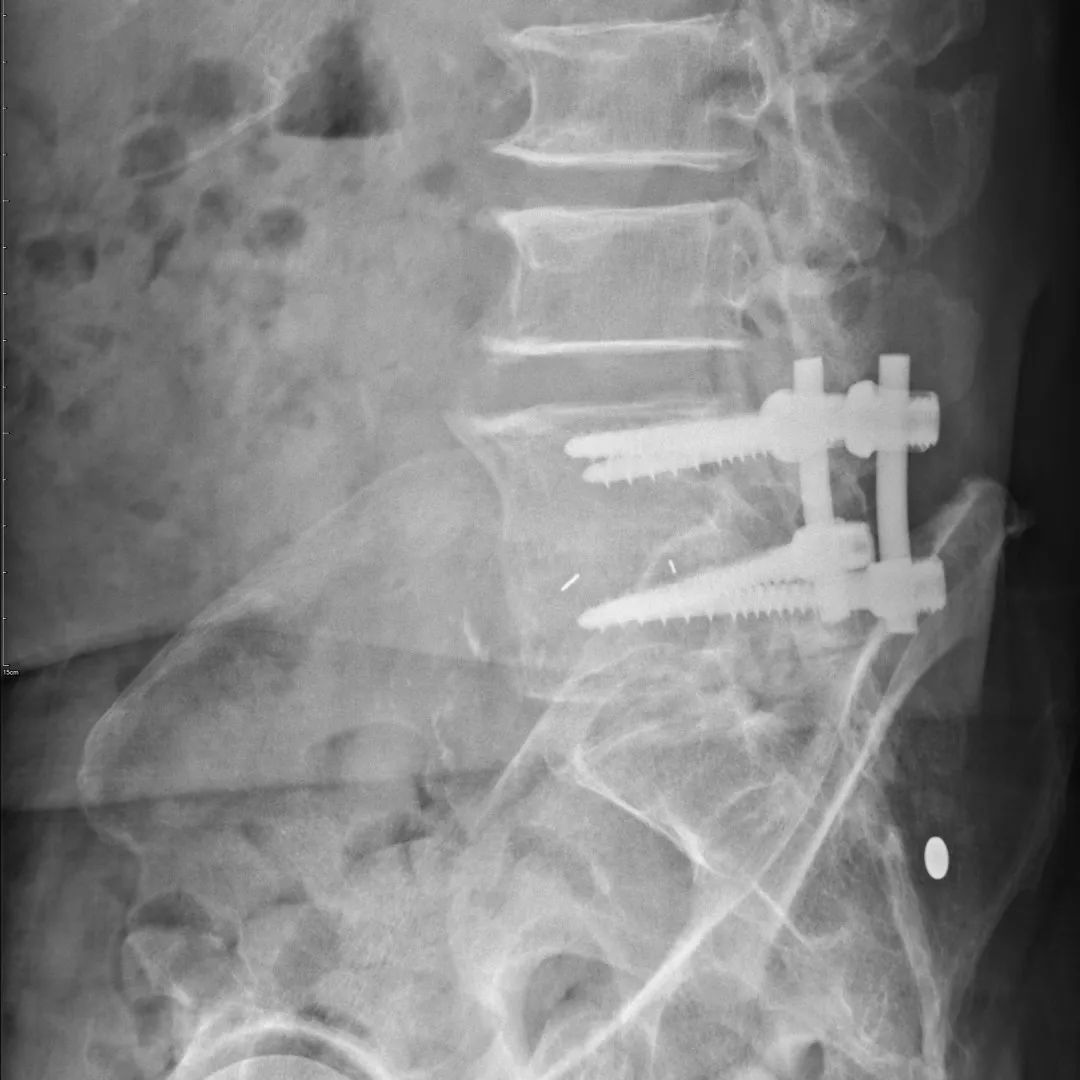

唐老伯7年前因为腰腿痛在外院做了“腰椎后路减压融合内固定”手术,术后症状明显缓解,本以为可以通过开刀一劳永逸的唐老伯没想到7年多之后腰椎再次出现问题,并且累及右腿疼痛难忍无法行走。

唐老伯外院术后影像